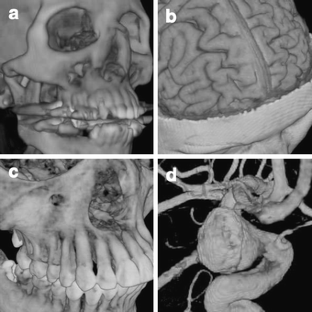

Fig 3.